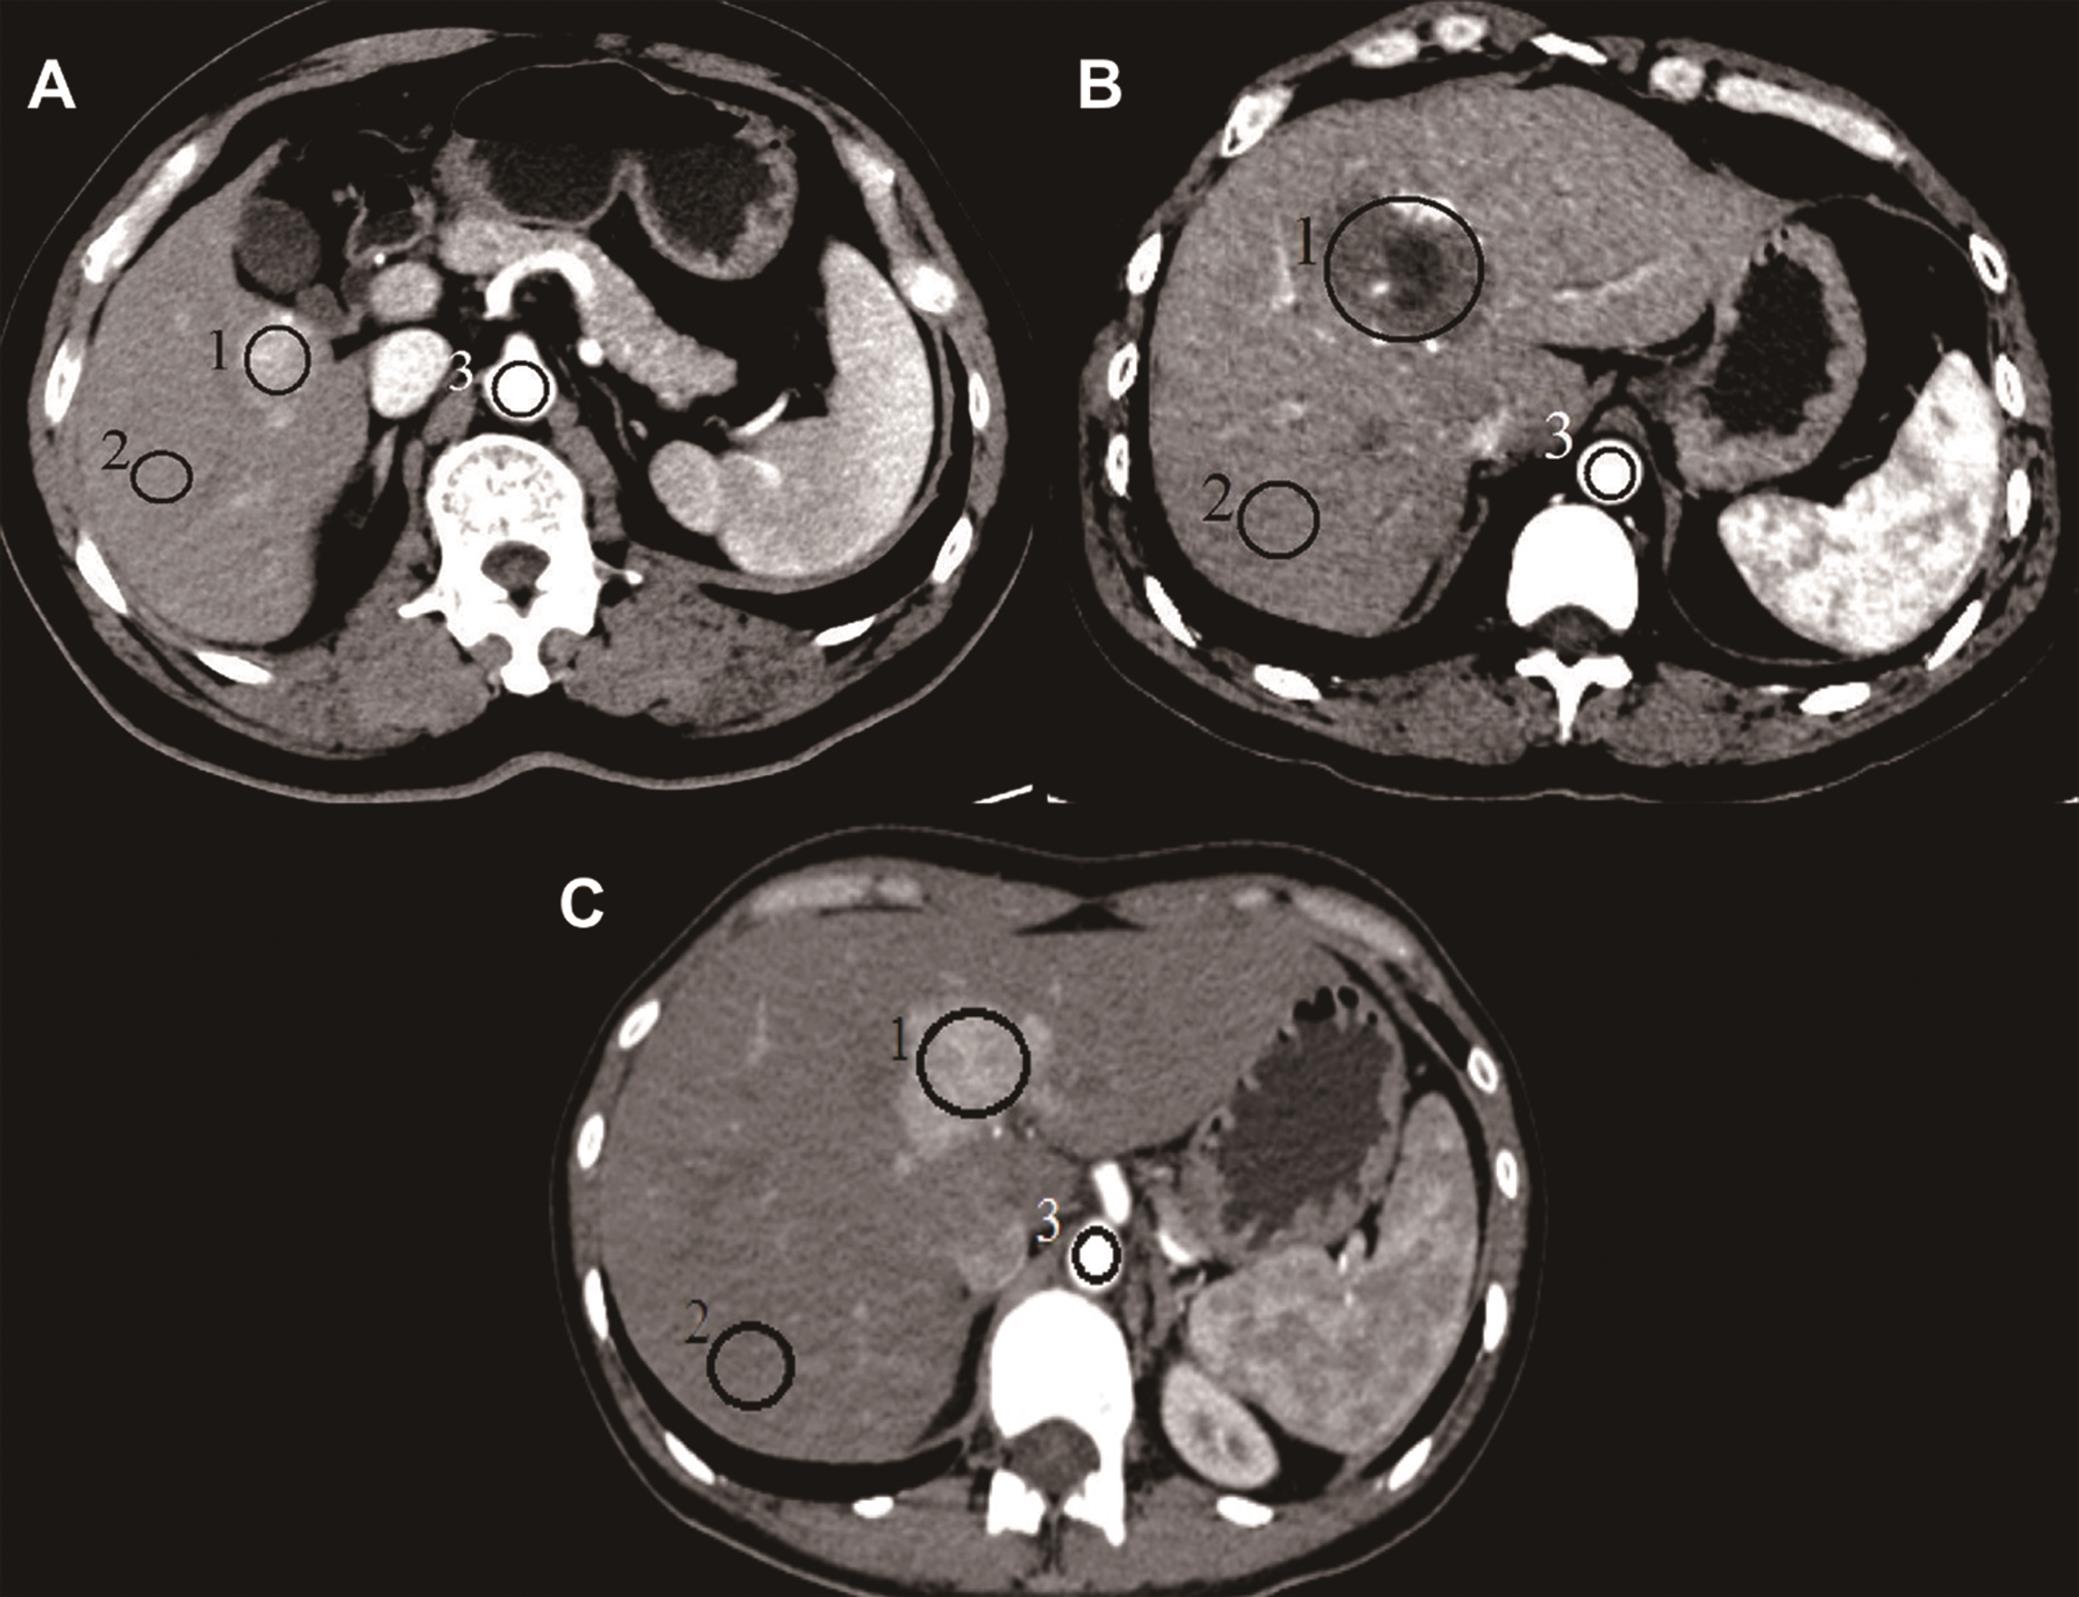

From www.researchgate.net

(A) CT finding of a large hemangioma occupying central and left liver Liver Hemangioma X Ray Hemangiomas of the liver are the most common type of benign liver tumor. Liver hemangiomas rarely cause symptoms, although large or multiple hemangiomas can. Hemangioma usually does not cause any symptoms or liver function impairment. Hepatic hemangiomas or hepatic venous malformations are the most common benign vascular liver lesions. Hepatic hemangioma (hh) is the most common benign liver tumor and. Liver Hemangioma X Ray.